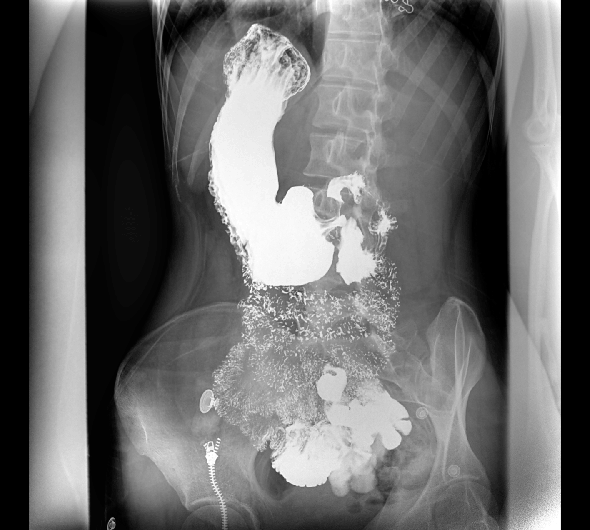

临床图像

创新动态断层多功能胃肠 DR 系列